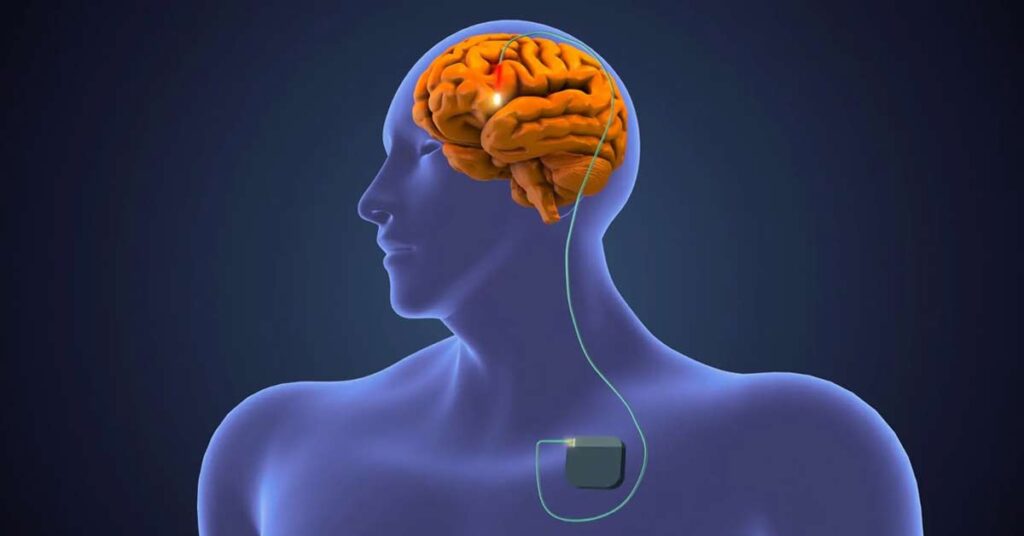

- Estimulação Cerebral Profunda (DBS): Cirurgia indicada em casos selecionados, que melhora tremores, rigidez e movimentos involuntários (discinesias).

Como é a cirurgia para Parkinson?

Sim. Existe uma cirurgia chamada Estimulação Cerebral Profunda, conhecida como DBS (do inglês, Deep Brain Stimulation).

Essa cirurgia não cura o Parkinson, mas ajuda muito a controlar os sintomas motores, como tremores, rigidez e lentidão, principalmente quando os remédios não estão mais funcionando tão bem.

Ela funciona como um “marca-passo” no cérebro. Pequenos eletrodos são implantados em regiões específicas, enviando estímulos elétricos que ajudam a regular os movimentos.

Nem todo paciente é candidato para a cirurgia. É necessário passar por uma avaliação criteriosa com o neurologista especialista em distúrbios do movimento.